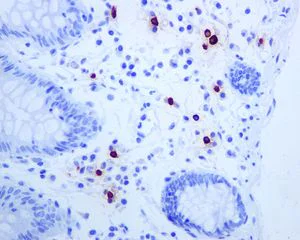

Immunohistochemistry (Formalin/PFA-fixed paraffin-embedded sections) - Anti-Mast Cell Tryptase antibody [EPR8476] - BSA and Azide free (AB227572)

Immunohistochemistry (Formalin/PFA-fixed paraffin-embedded sections) analysis of Human stomach tissue sections labeling Mast Cell Tryptase with Purified ab134932 at 1 : 5000 dilution (0.65 μg/ml). Heat mediated antigen retrieval was performed using ab93684 (Tris/EDTA buffer, pH 9.0). ImmunoHistoProbe one step HRP Polymer (ready to use)was used as the secondary antibody. Negative control : PBS instead of the primary antibody. Hematoxylin was used as a counterstain.

This data was developed using the same antibody clone in a different buffer formulation containing PBS, BSA, glycerol, and sodium azide (ab134932)